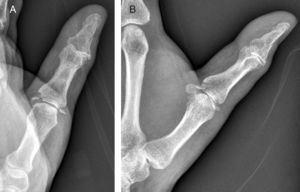

Caso clínicoPaciente de 56 años, en estado etílico, es trasladado a Urgencias con una herida contusa en la nariz tras una caída al suelo. Después de suturarla, se decide su observación durante unas horas. En el momento del alta, el paciente se queja de su mano izquierda, la cual se encuentra, a nivel del pulgar, inflamada y equimótica, con una erosión de 0,5cm2 situada en el lado radial de la articulación MCF. El estudio radiográfico muestra fractura-avulsión de ambos ligamentos colaterales de la articulación MCF del pulgar (fig. 1). Con anestesia troncular axilar, se explora mediante control fluoroscópico la estabilidad de la articulación y se comprueba que tanto en extensión como en flexión de 30° no existen bostezos apreciables que denoten la total rotura de los ligamentos colaterales, motivo por el cual se decide el tratamiento conservador mediante un yeso de escafoides durante 4 semanas, tras las cuales se permite la movilidad libre del pulgar. Un año más tarde, el paciente se halla libre de dolor y sin inestabilidad. Sin embargo, el estudio radiográfico objetiva la existencia de una falta de unión en ambas fracturas (fig. 2).